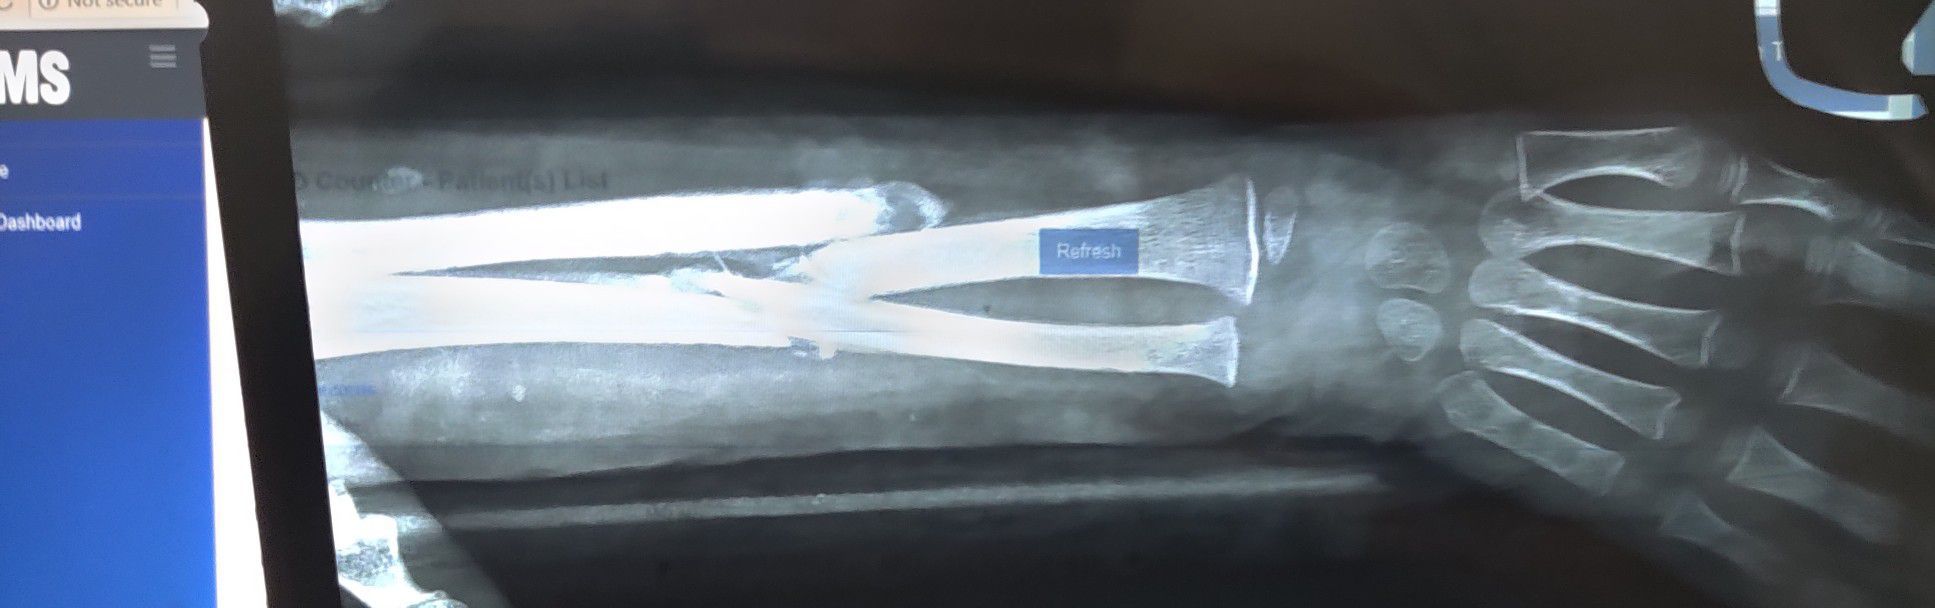

Fracture Radius + Ulna

Radius

Ulna